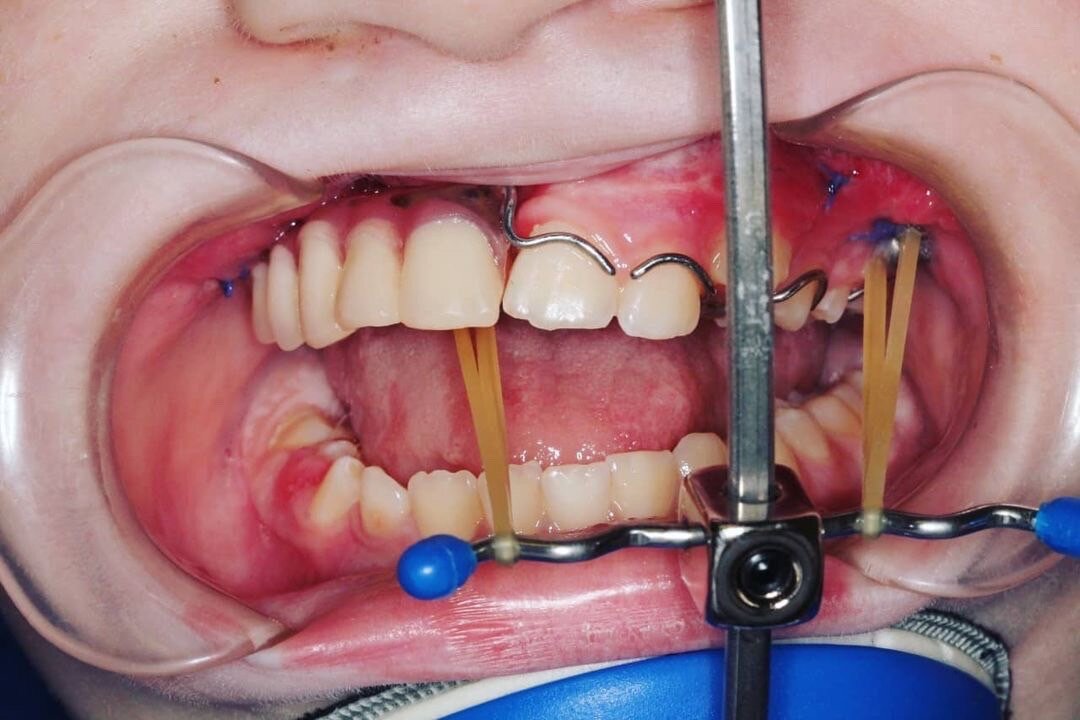

Вторым этапом был изготовлен съёмный протез на место удалённой челюсти для социализации (сохранить эффект целостнлсти верхней челюсти и зубов), нормального функционирования и для предотвращения вторичной деформации (смещения зубов).

В последствии это приведёт к деформации лица. Поэтому наша задача и цель - попытаться стимулировать рост верхней челюсти. Для этого на верхнюю челюсть установили титановые имплантаты. К ним крепится внеротовая тяга (маска). Эту маску ребёнок одевает на ночь и днём пока находится дома. В среднем 14-18 часов.

Что бы можно было использовать эту конструкцию одновременно со съёмными протезами в съёмных протезах сделали специальные отверстия.